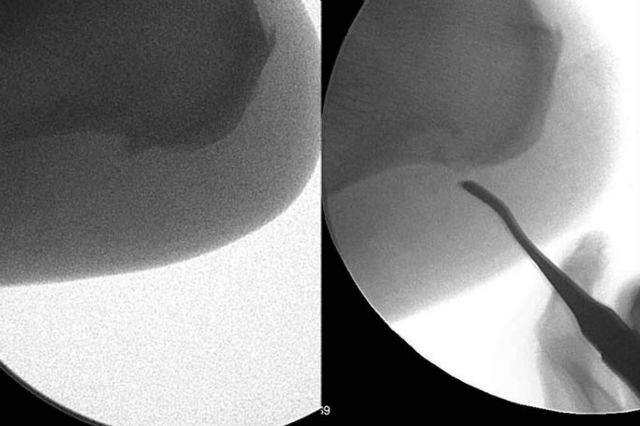

Para ello, los podólogos en Donostia de Clínica del Pie Ariño guiados en todo momento por un ecógrafo de alta definición realizan una liberación parcial de la fascia plantar y eliminación del espolón calcáneo, con una incisión de 2 mm, sin necesidad de poner puntos. Después de la intervención, el paciente sale caminando del quirófano por su propio pie, con un vendaje y calzado especial, sin necesidad de muletas ni bastones. Es un procedimiento ambulatorio que asegura una recuperación rápida.

A diferencia de la cirugía convencional, en la cirugía ecoguiada se utiliza anestesia local, la recuperación postquirúrgica es muy rápida, el sangrado y el dolor es mínimo, no se ponen puntos ni isquemia, la cicatrización es muy rápida, reduciendo el riesgo de infección y problemas circulatorios. Se trata de una intervención rápida y sencilla que dura 45 minutos aproximadamente. Es una técnica indicada cuando los tratamientos conservadores no hayan funcionado y el paciente lleve más de 6 meses con molestias. Es muy importante realizar un buen diagnóstico previo, ya que en ocasiones acuden a consulta fascitis plantares mal diagnosticadas, con síntomas parecidos a la fascitis plantares, pero que no son y es necesario acudir a un especialista que realice un diagnóstico diferencial mediante el uso de la ecografía, radiografías o resonancia magnética nuclear.